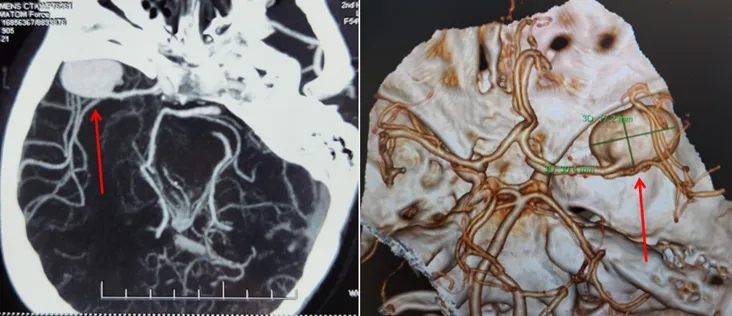

患者右颞部搏动性剧痛10天,遍访多家医院未果,慕名到我院神经外科五病区求医。张更申、吴建梁教授凭借丰富经验迅速为患者安排了头CTA检查,发现其右侧大脑中动脉有一枚直径达30mm的巨大动脉瘤,远超常规大小,已至破裂边缘,情势危急,决定立即手术,预防致命出血。

神经外科五病区迅速启动预案,紧急收治患者并进行脑血管造影等术前检查,精确诊断复杂动脉瘤位于右脑中动脉M1-2分叉,手术难度极高、风险巨大。